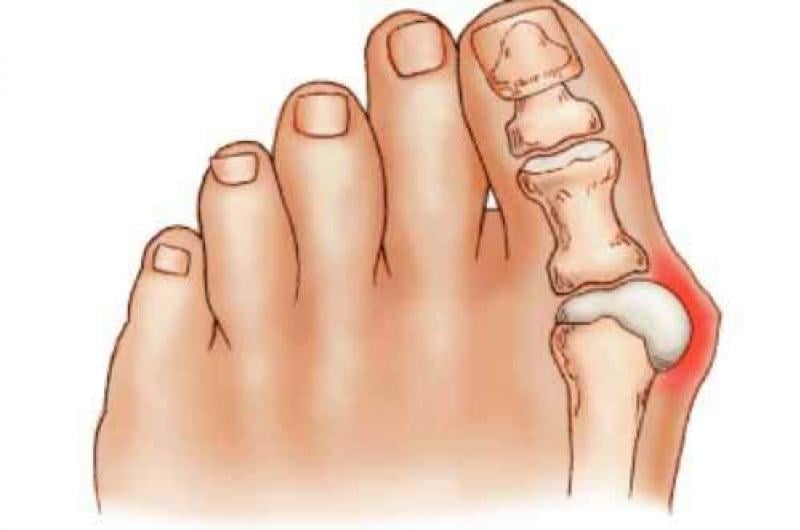

Deformidades como juanetes y dedos en martillo

El uso de zapatos convencionales también puede contribuir al desarrollo de deformidades en los pies, como juanetes y dedos en martillo.

Los juanetes son protuberancias óseas que se forman en la base del dedo gordo del pie. Se desarrollan cuando el dedo gordo se desvía hacia los demás dedos del pie, lo que resulta en la formación de una protuberancia en el lateral del pie. El uso de zapatos que no proporcionan suficiente espacio para los dedos del pie puede empeorar el desarrollo de juanetes.